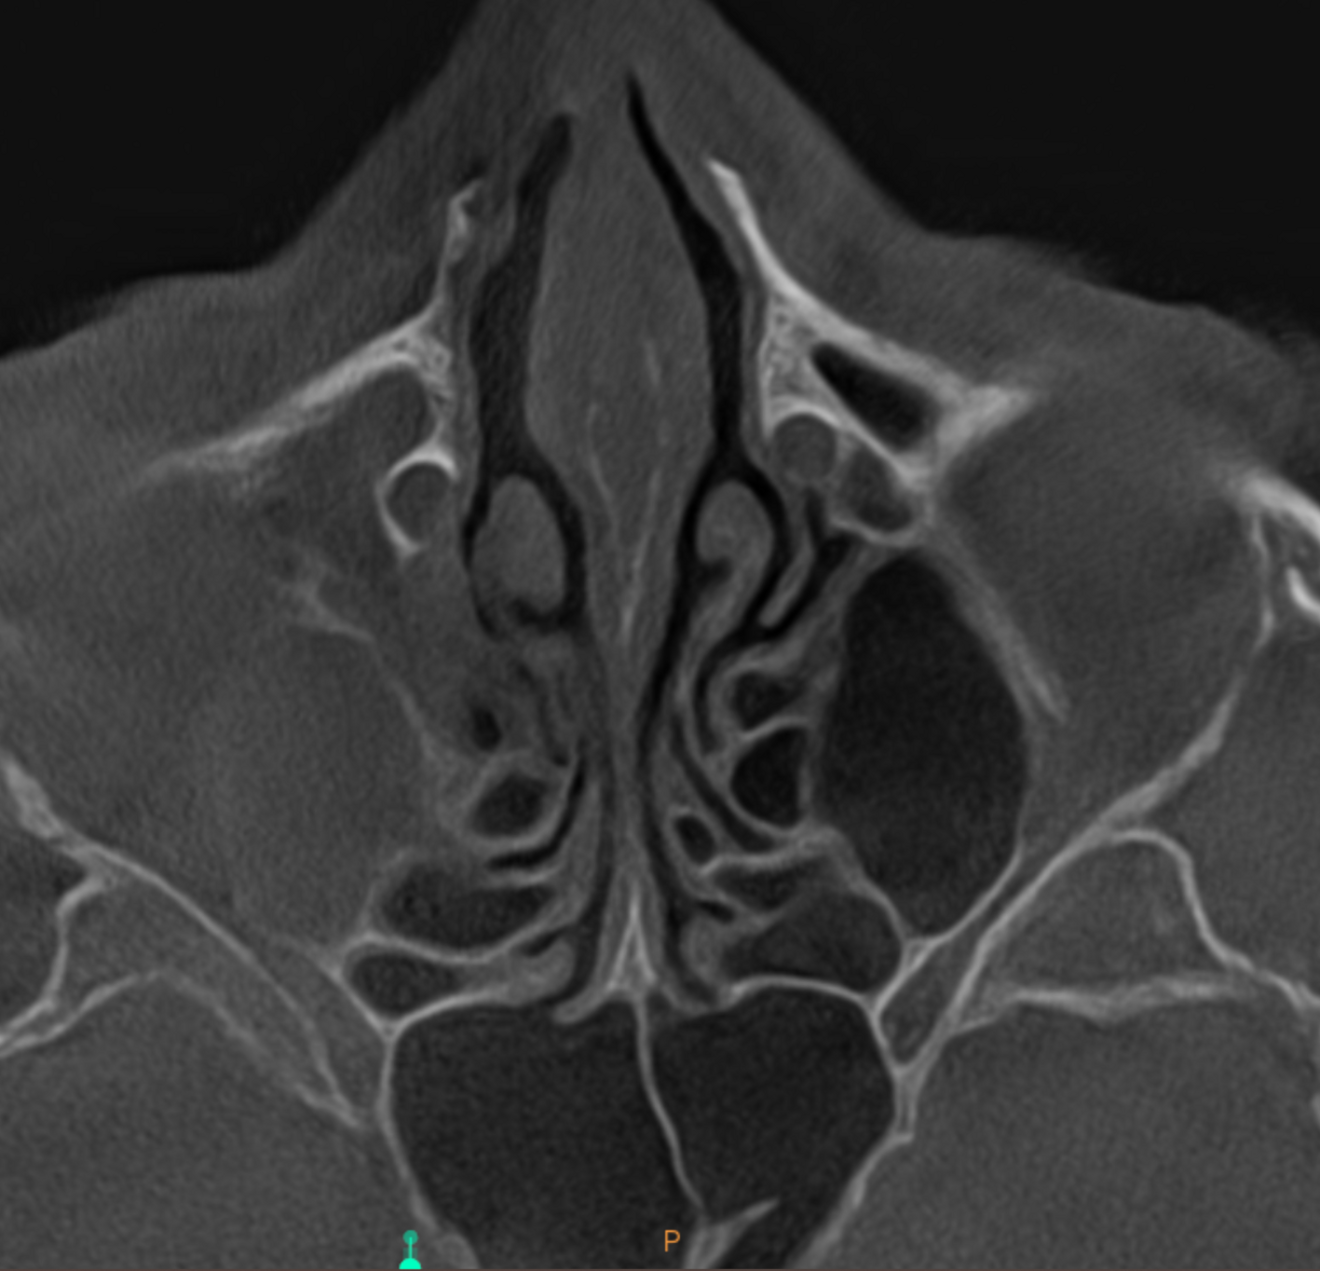

Fig. 3: Large-volume CBCT scan, frontal cross-section showing increased radiopacity in the paranasal sinus area.

The extent of the inflammation was shocking (Figs. 2a & b). Not only the maxillary sinus (Fig. 3) but the ethmoid and sphenoid sinuses too were involved, and the inflammation had spread towards the right cavernous sinus as well (Fig. 4). At this point, extraction may have been the first choice for most dental clinicians, but we had to keep in mind that invasive treatment may have increased the risk of cavernous sinus thrombosis, a potentially avoidable possibility. There are very few circumstances under which a dental procedure can cause very severe or even lethal consequences, but this case approached such a situation.

Fig. 5e: High-level transversal cross-section of the maxilla showing involvement of the sphenoid and ethmoid sinuses.

Fig. 5f: Very high-level transversal cross-section of the maxilla showing involvement of the lower part of the cavernous sinus.